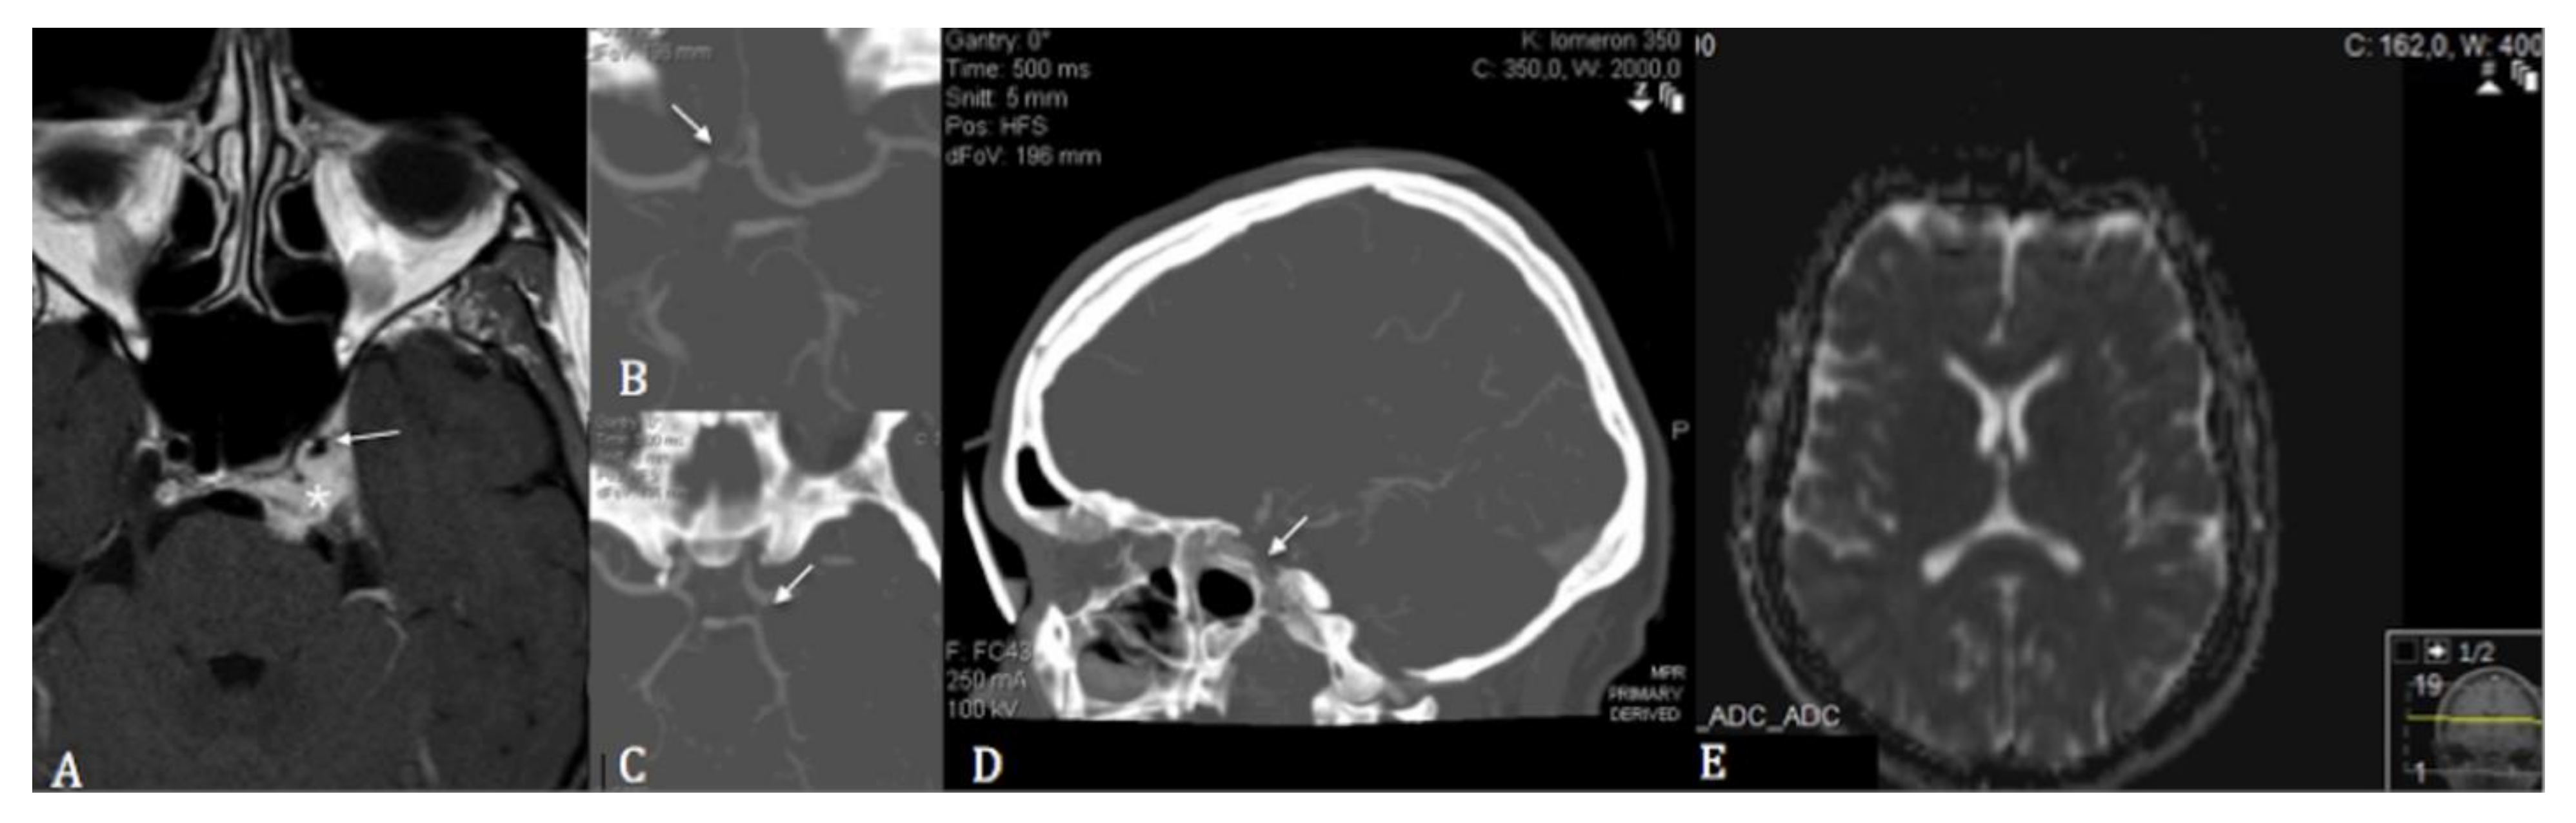

2. Case Description